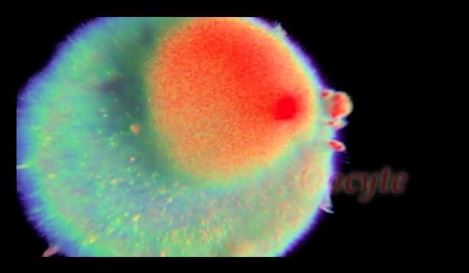

Παρακολουθείστε μέσα σε 4 λεπτά, όσα συμβαίνουν στο γυναικείο σώμα, επί 9 μήνες. Από τη στιγμή που θα γονιμοποιηθεί το ωράριο, μέχρι τη στιγμή που το βρέφος θα είναι έτοιμο να βγει από την κοιλιά της μητέρας του.

Δείτε σε μια απίστευτη απεικόνιση του Έλληνα καθηγητή Αλέξανδρου Τσιάρα, πως διαιρούνται τα κύτταρα, πως σχηματίζεται ο εγκέφαλος, τα μάτια, τα χεράκια, τα γεννητικά όργανα του εμβρύου και πως το μωράκι όταν βγαίνει, “τινάζει” τα ποδαράκια του για να βοηθήσει τη μητέρα στις εξωθήσεις.